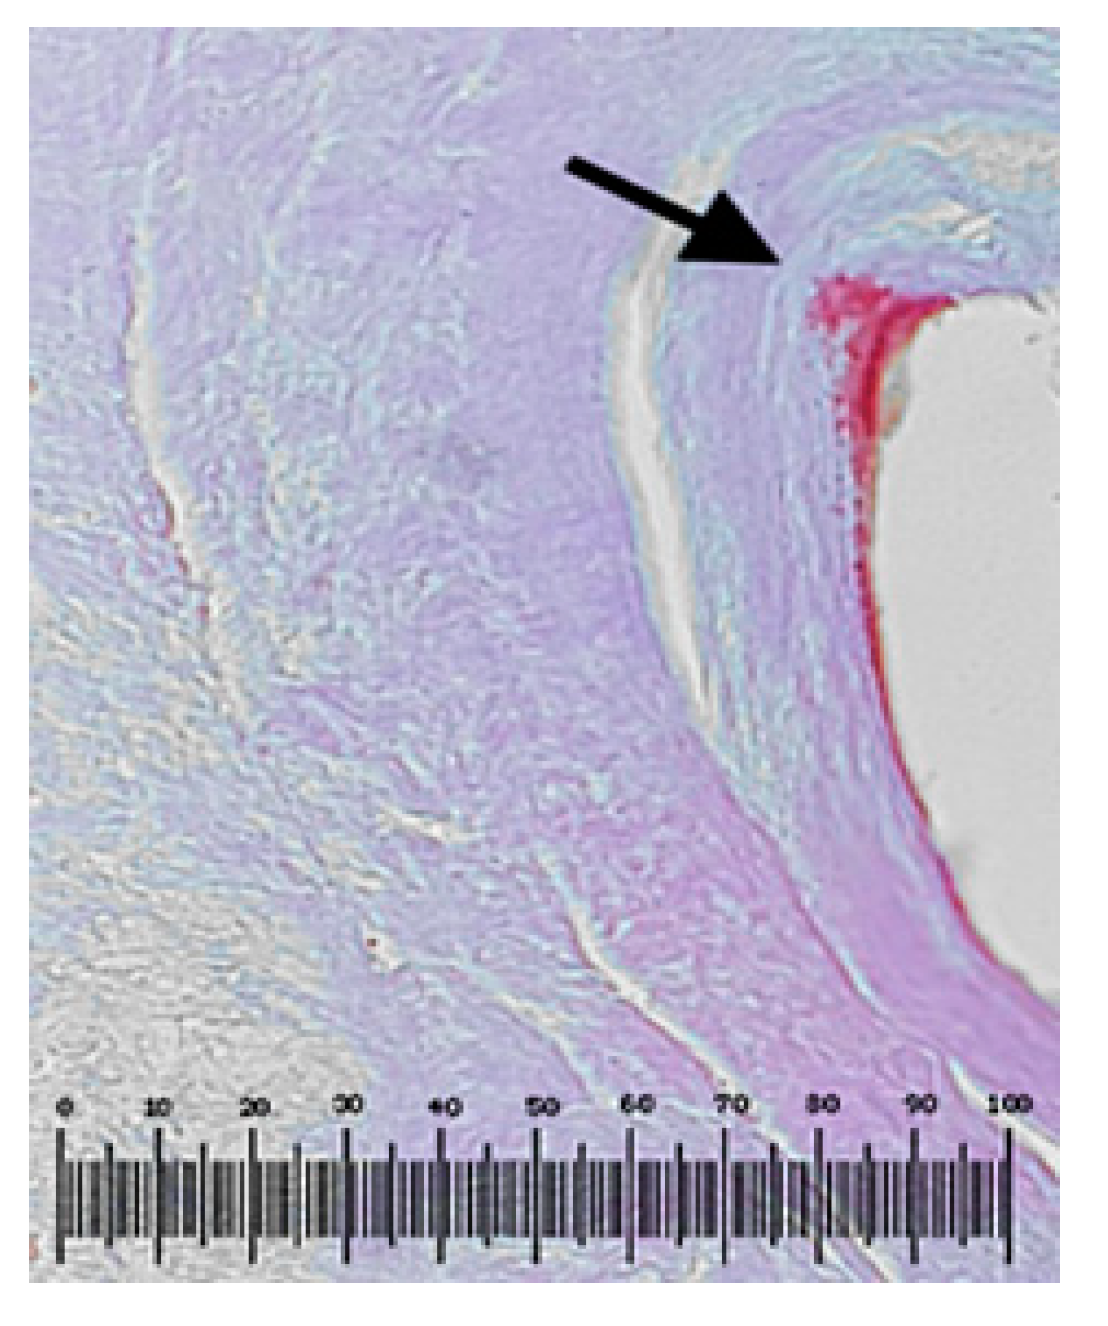

The tissue samples were subjected to anatomopathological investigations according to the protocols mentioned in the subchapter Materials and Methods. For upstream sample P11, the following images presented in Figure 12 were obtained.

Figure 12.

Rigid ecaudate arteriosum (concentric and predominantly left) fibrosis and calcifications (marked by arrow) that have surrounded one of the stents taken; the polarized light exam did not reveal fragments from the stent in peripheral tissue; hematoxylin–eosin staining; magnification × 200.